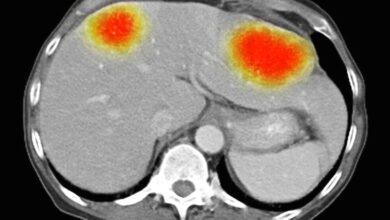

جزيئات ذهب «مكهربة» لعلاج السرطان

تمكن باحثون من استخدام جزيئات صغيرة من الذهب، مشحونة كهربائياً، لخداع الخلايا في أحد أكثر أنواع السرطان فتكاً كي تقوم…